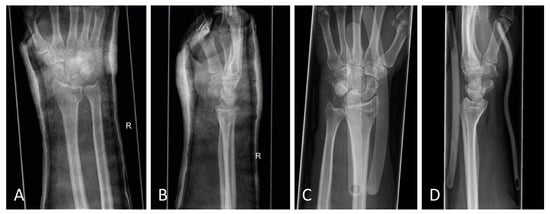

Figure 6.

(A) Posteroanterior radiograph with cast. (B) Mediolateral radiograph with cast. (C) Posteroanterior radiograph with orthosis. (D) Mediolateral radiograph with orthosis. All radiographs were taken after reduction before surgery.

The standard treatment approach in our Level I trauma center was not altered by the study protocol, except from the placement of the orthosis. In our approach, we were able to adjust the orthosis used immediately during finger-trap traction and show that there was no increase in secondary dislocations on the radiographic and CT control imaging and, moreover, that diagnostic procedures were in no way restricted when the orthosis was in place. The quality of detail was not limited in any way in the lateral projection, very less in the posteroanterior view (Figure 6A–D). Additionally, the use of the orthosis did not affect the CT scan. As shown in Figure 7, there are no metal artifacts induced by the aluminum splints. Hence, modern orthoses enable comprehensive radiographic diagnostics.